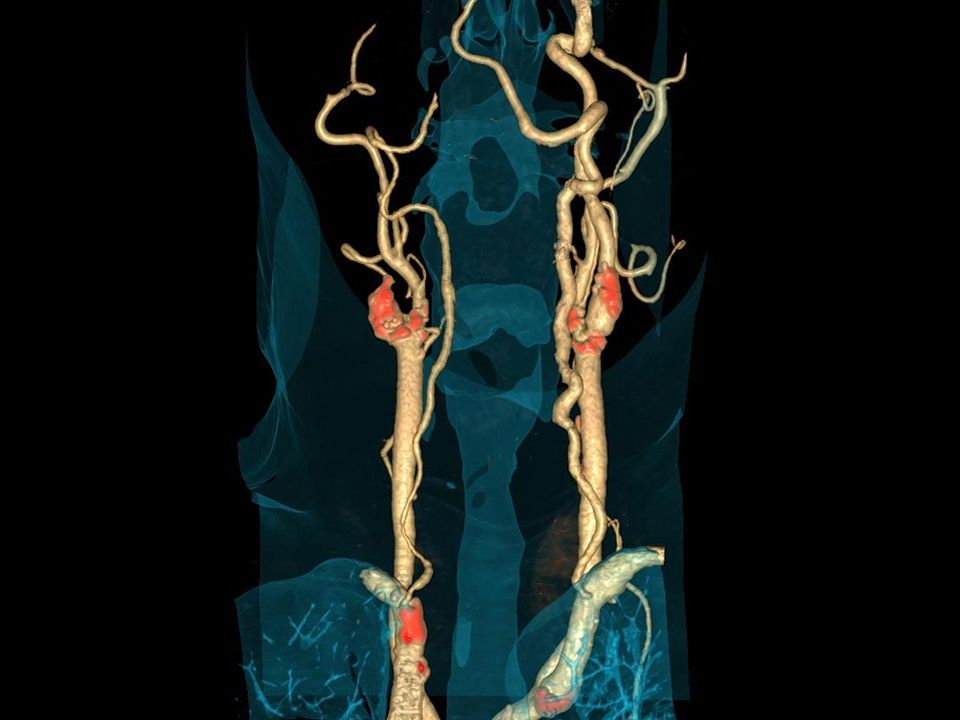

CT DE Direct Angio

Accurate bone removal even in complex body regions.